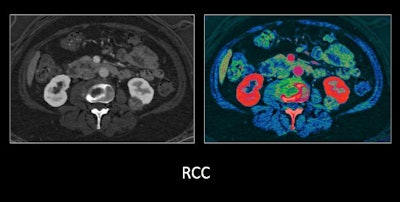

- Improved lesion detection: Low-energy scans are particularly optimal for the attenuation of iodine contrast. And this improved contrast visualization can facilitate the detection of small, difficult-to-find lesions by increasing their visibility and reducing the pseudoenhancement often seen surrounding kidney and liver lesions.

Improved lesion characterization: Furthermore, clinicians can create virtual monochromatic images from the DECT dataset to enhance the visibility of obscure findings that would otherwise prove difficult to characterize on conventional CT. Patel and colleagues came across several instances where a liver tumor could have been either benign or malignant on standard contrast-enhanced CT.

"We used dual-energy CT to help radiologists better and more confidently distinguish and differentiate benign from malignant lesions," he said.